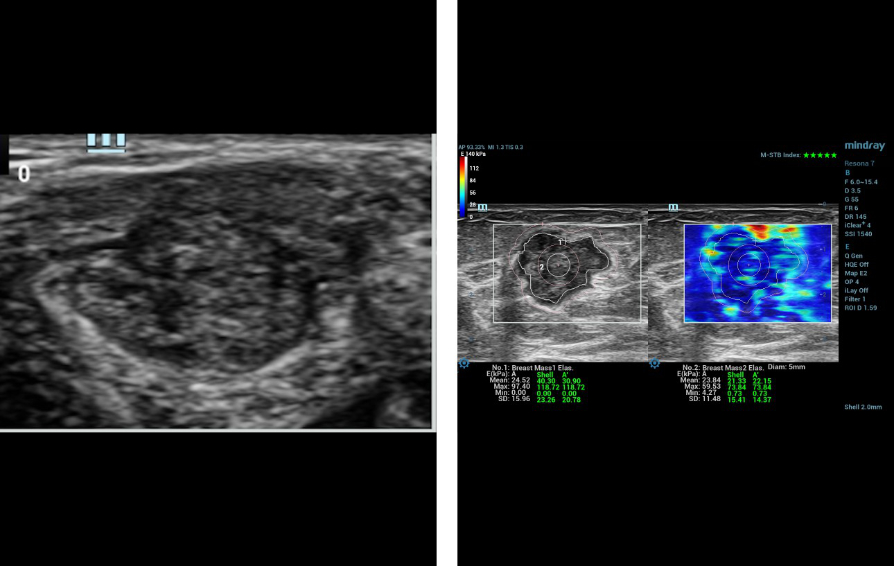

Mindray commenced its first #Nuewa Club Meeting in Bucharest, Romania!

Bajo el tema ŌĆ£inspirando el cuidado de la salud de la mujerŌĆØ, se llev├│ a cabo en la Ciudad de Panam├Ī la primera conferencia de Nuewa Club en Latino America.?